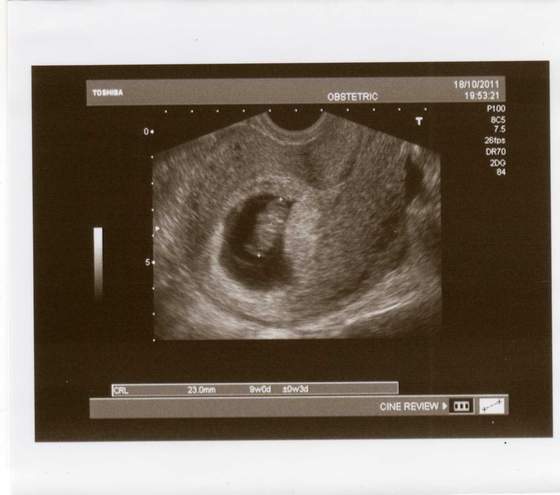

Następna wizyta nie wiem kiedy chciał abym za 2 tyg przyjechała ale 30 chyba jedziemy do Alberta więc na telefon jestem z nim umówiona jak wrócę dam mu znac i wtedy się umówimy tylko mam cukrów pilnować i jeśli tam będa rosły sama mam dawke insuliny podnieść. Ja mam jutro wizytę u Ginekologa na 15.40 trzymajcie kciuki aby Szymonek rósł zdrowo